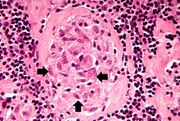

| 03:39, 19 August 2013 | IPLab3Tuberculosis4.jpg (file) | 66 KB | Seung Park | This is a high-power photomicrograph of a granuloma. Note the necrotic core on the right (1), epithelioid macrophages (2), and Langhans’ type giant cells (3) at the periphery of the granuloma. Note also the small lymphocytes characterized by their di... | 1 | |